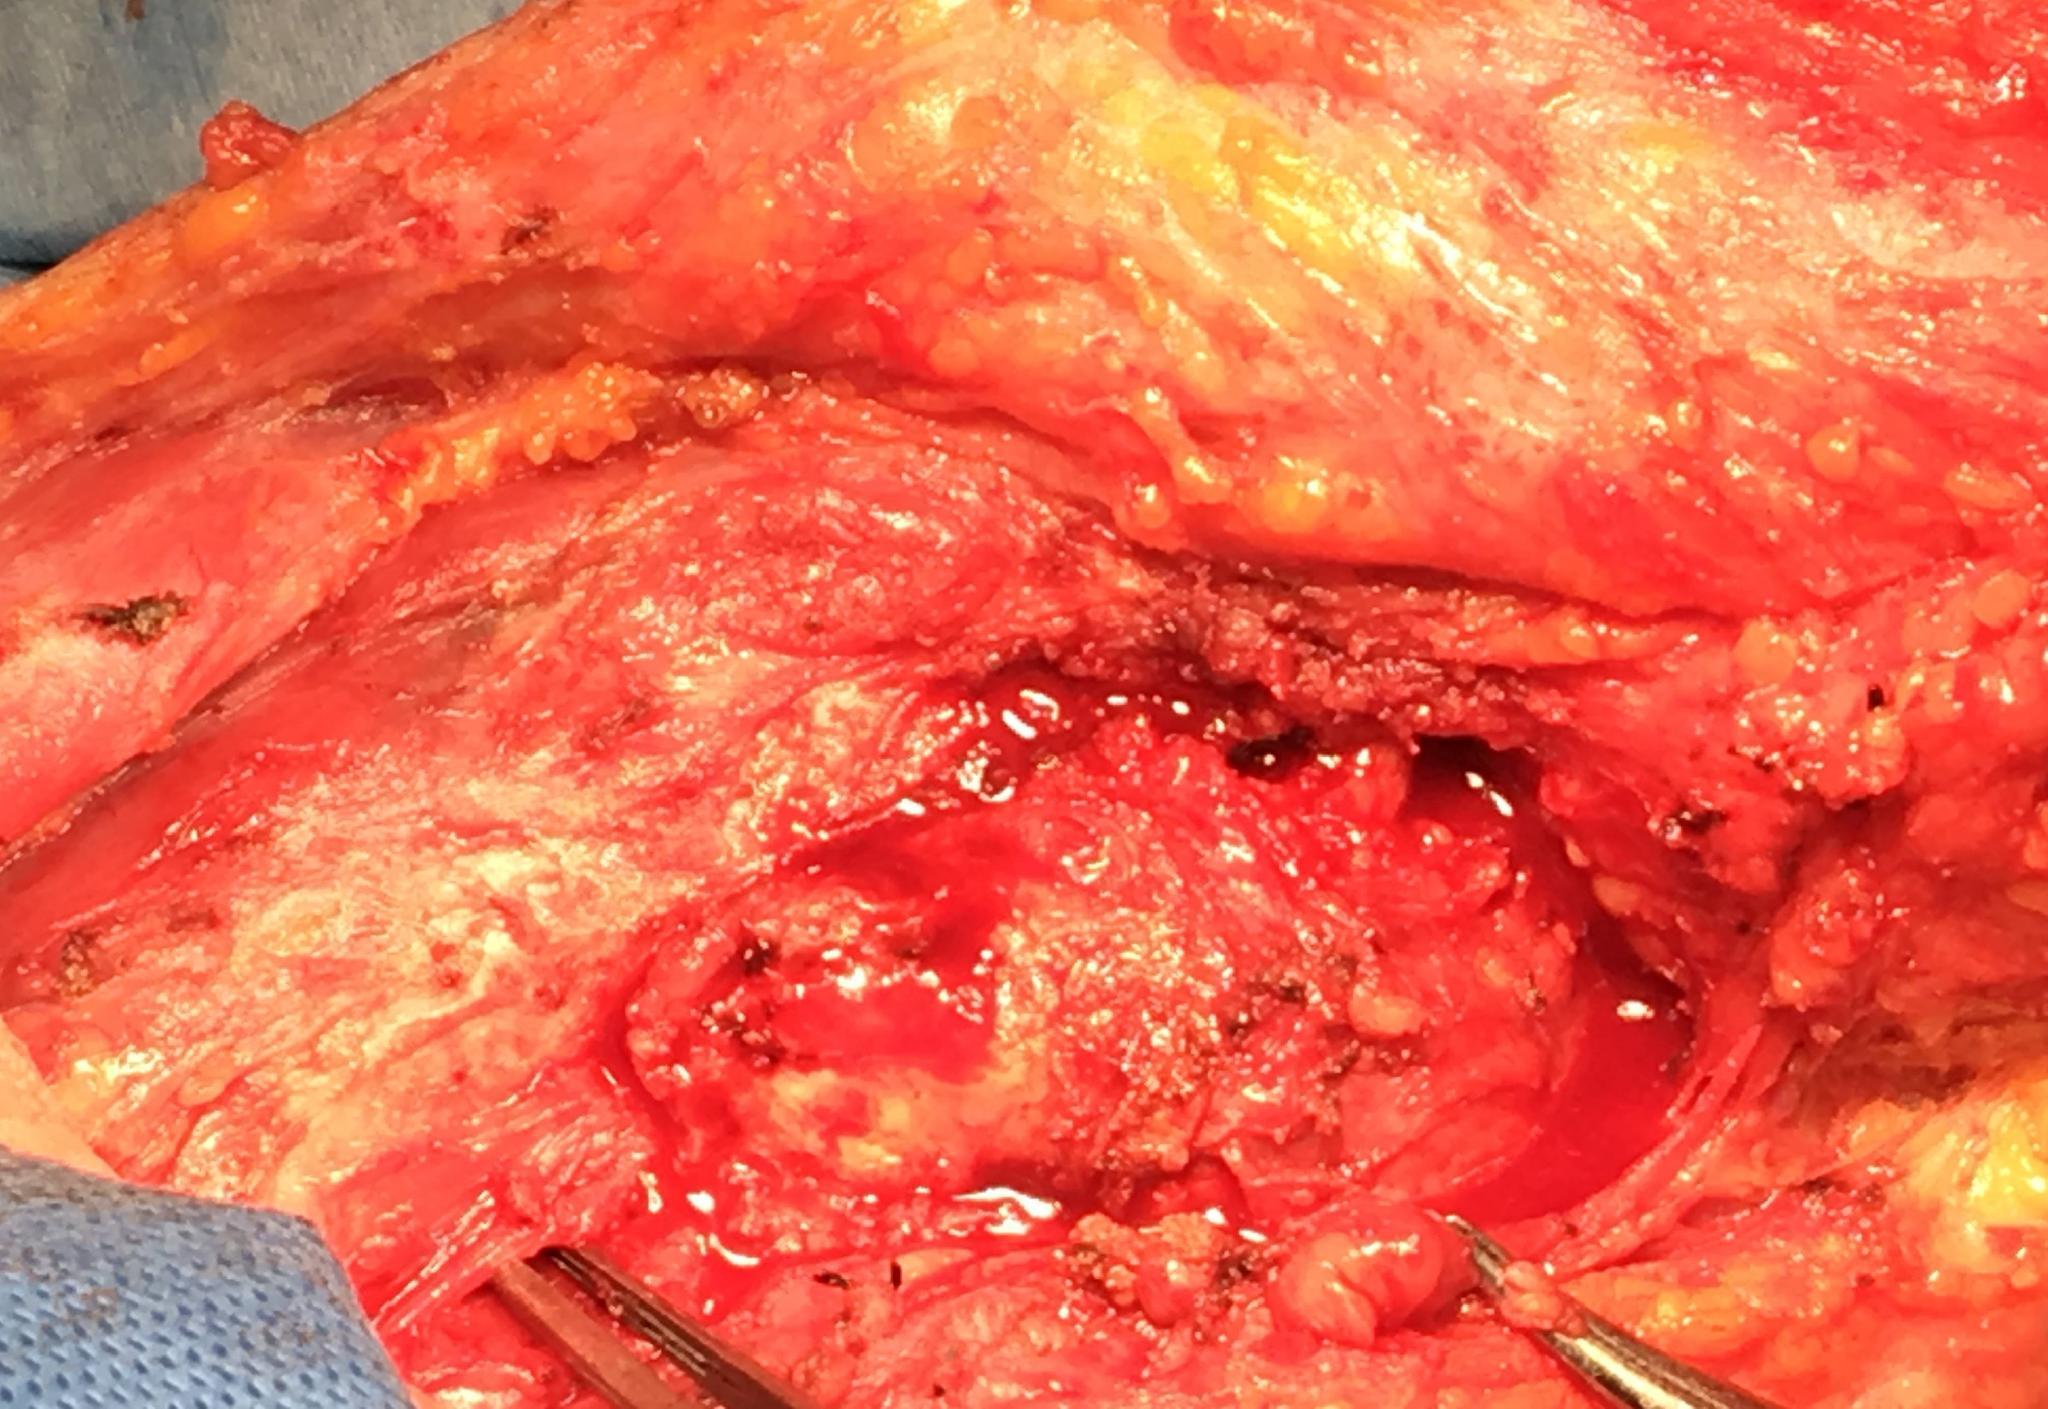

手術割下來的喉腫瘤

切下來的喉腫瘤

切除喉腫瘤